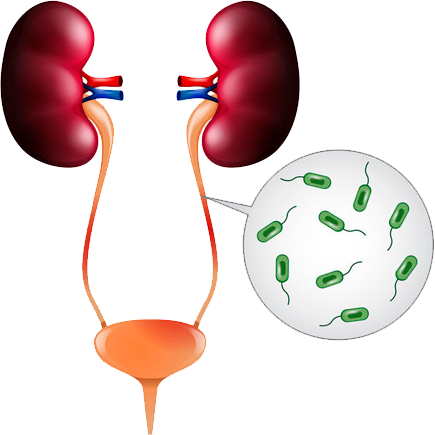

Tengo como compromiso mejorar la salud de nuestra comunidad y promover la prevención de patologías que afectan al aparato urinario, glándulas suprarrenales y retroperitoneo de ambos sexos, y el aparato reproductor masculino.

“Gracias a la prevención, el doctor pudo identificar una infección en etapa temprana”

- Lourdes Campos Uribe